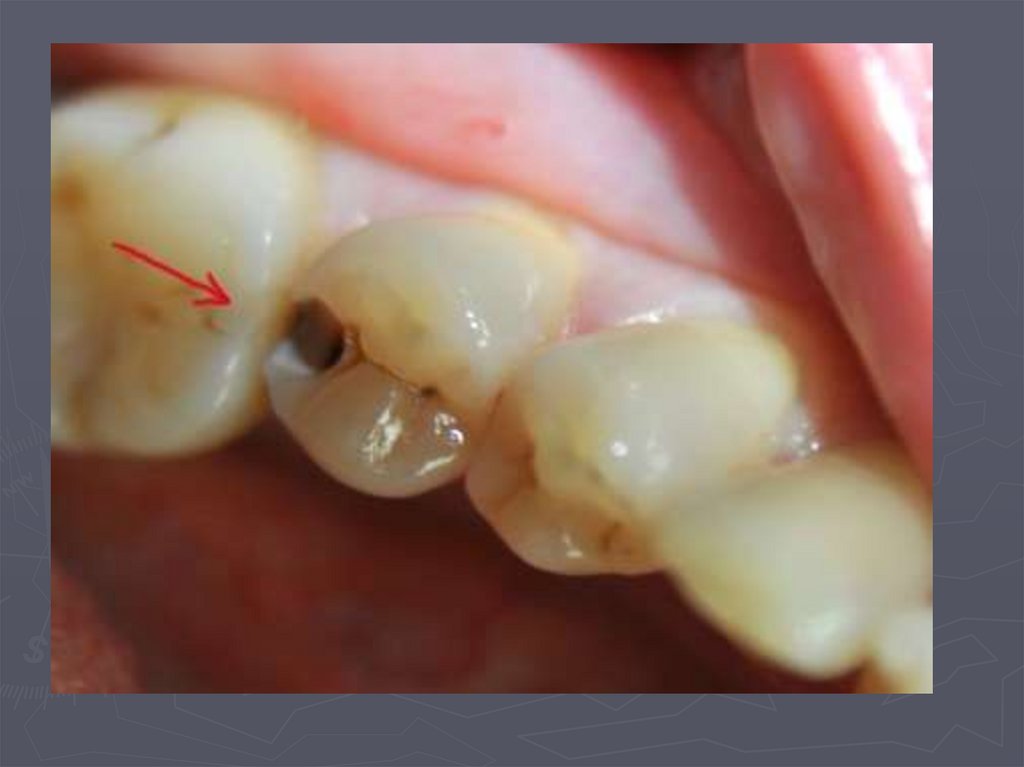

37. КЛИНИЧЕСКАЯ КАРТИНА СРЕДНЕГО КАРИЕСА при компенсированной форме:

► отмечается быстропроходящая боль от

химических, термических, иногда от

механических, раздражителей;

► края кариозной полости закругленные, ровные;

► эмаль плотная;

► дентин плотный, пигментированный;

► при зондировании болезненность определяется

по эмалево-дентинному соединению.

38. КЛИНИЧЕСКАЯ КАРТИНА СРЕДНЕГО КАРИЕСА при декомпенсированной форме:

► при локализации кариозной полости в фиссурах

определяется небольшое входное отверстие;

► при раскрытии обнаруживается кариозная

полость с податливым дентином;

► края кариозной полости нависают;

► эмаль тонкая, хрупкая;

► дентин светлый, влажный, размягченный, легко

удаляется экскаватором;

► зондирование болезненно по

эмалево-дентинному соединению.